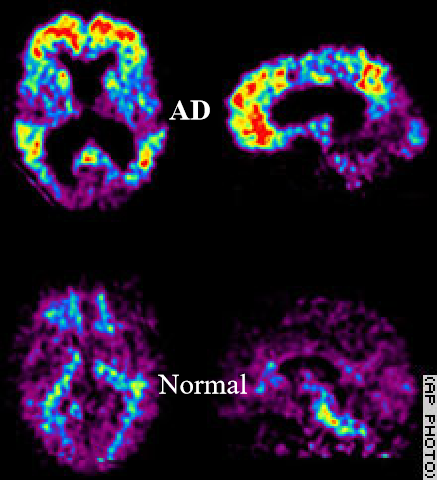

当前,阿尔茨海默症的诊断主要靠两种检测方法,一种是脑脊液AD标志物检测,另一种是通过PET扫描仪的脑成像检测。在2018版的权威指南里,已将这两种检测作为诊断阿尔茨海默病的“金标准”。

PET检查需要在血液内注入放射性物质,然后再做脑扫描,需要做3次,对身体也有一定的损伤,而且价格昂贵。

▲PET扫描显示结果